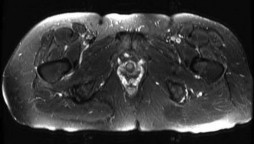

Question 5:

A 24-year-old collegiate hockey player presents with persistent anterior groin pain exacerbated by hip flexion and internal rotation. Radiographs demonstrate an alpha angle of 72 degrees on the Dunn view. Which of the following best describes the primary pathomechanical pattern of chondral damage associated with this morphology?

Correct Answer: Delamination of the anterosuperior acetabular cartilage due to outside-in shear forces

Explanation:

An alpha angle > 55 degrees indicates Cam-type femoroacetabular impingement (FAI). Cam morphology causes outside-in shear forces against the anterosuperior acetabular rim during hip flexion and internal rotation. This selectively damages the transitional zone cartilage, causing delamination of the articular cartilage off the subchondral bone while often leaving the labrum initially intact. Pincer impingement typically causes labral crushing and contrecoup chondral lesions.